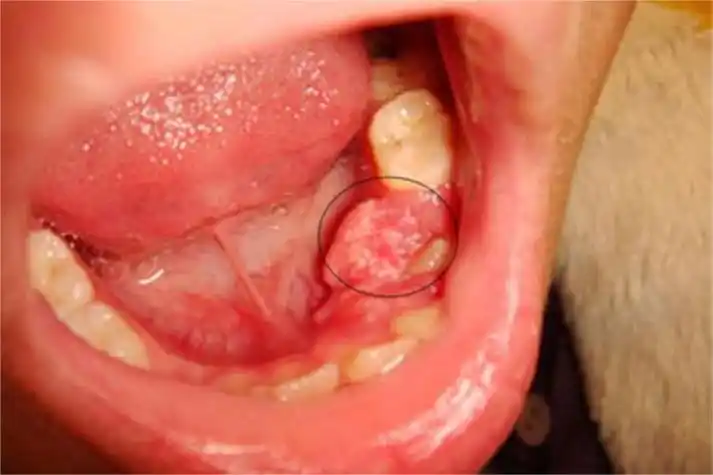

牙龈癌牙齿脱落图肉芽粒状溃疡图菜花状溃疡图牙龈癌早期常侵犯牙槽突

牙龈癌早期症状图片(55)

牙龈癌早期症状图片(25)_有来医生